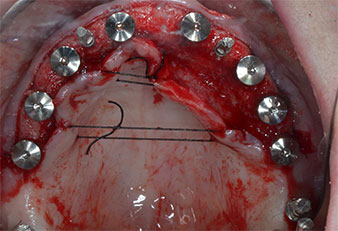

Tres años después, llegó el momento de colocar una prótesis del mismo tipo en el maxilar superior. Basándose en una planificación mediante tomografía computarizada de haz cónico (CBCT, por sus siglas en inglés), se evitó la necesidad de realizar una elevación del seno utilizando implantes cortos, mientras que una plantilla quirúrgica sirvió para transferir las posiciones planificadas al borde alveolar (figuras 1 y 2).

Para marcar las posiciones del implante y realizar la preparación piloto, se utilizó un inserto piezoeléctrico (Piezomed I1) con revestimiento de diamante y forma de llama (figura 3). Se tomaron precauciones para realizar movimientos hacia arriba y hacia abajo, con una potencia reducida, una irrigación completa y una baja presión (por debajo de 300 g). A continuación, se aplicó un inserto piloto (Piezomed I2A/I2P) para aumentar el diámetro inicial de 2 mm de los sitios de implante (figura 4), seguido de un inserto de 3 mm (Fig. 5).

En el caso que nos ocupa, no se utilizaron los insertos Z25P ni Z35P debido a la existencia de un hueso posterior relativamente blando, que se trató sin problemas con el I3A/I3P.

Debido al hueso relativamente duro (D2) existente en el sector anterior, los sitios de los implantes largos de 10 mm de las posiciones 11 y 21 se finalizaron con una fresa rotatoria de 4 mm de diámetro, en combinación con un contra-ángulo quirúrgico WS-75 L de W&H, el motor de implantes Implantmed de W&H y el módulo opcional Osstell ISQ de W&H. En cambio, debido a la existencia de hueso blando, los sitios posteriores se prepararon hasta un diámetro final de 3 mm utilizando el inserto Piezomed I3P. Por último, los implantes se colocaron a nivel crestal para su osteointegración durante tres meses (figuras 6-10). La prótesis existente se mantuvo sobre cuatro implantes provisionales (figura 8).